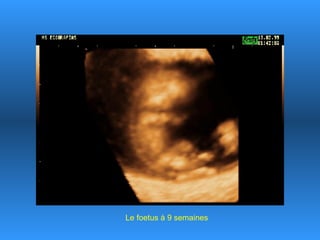

Le document traite des progrès scientifiques réalisés dans le domaine des échographies 3D. Il montre l'évolution des images du fœtus à différentes étapes gestationnelles, illustrant la clarté des images obtenues au fil du temps. Cette avancée technologique est présentée comme impressionnante, notamment pour le fœtus de 18 ans.